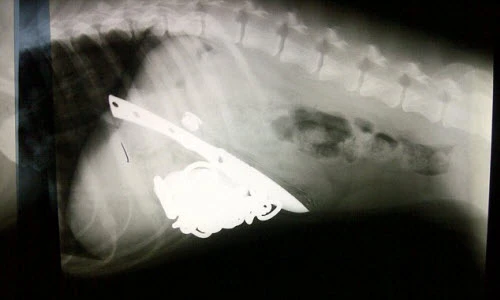

Dị vật trong bụng một con chó bull khiến ai cũng sửng sốt. Chú ta nuốt cả dao săn và dây xích vào trong bụng.

Sau khi phẫu thuật, bác sĩ đã lấy khỏi dạ dày con chó bull nhiều dị vật bao gồm: dao, dây xích, bao thuốc lá, tuýp thuốc, lá cây và những mảnh gỗ nhỏ.

Ảnh X-quang cho thấy cả một con dao thái bánh mì nằm trong bụng chó.

Con dao thái bánh mì dài tới 12 cm.